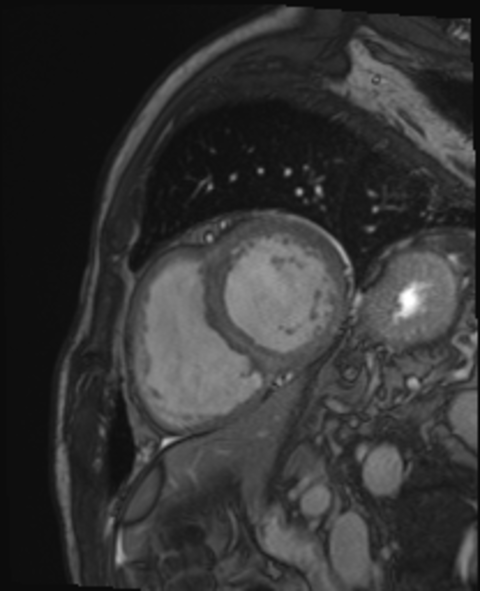

Die MRT bietet die Möglichkeit die Anatomie des Herzens, die Funktion der Herzkammern und die Morphologie des Herzmuskels detailliert darzustellen. Dazu arbeitet die Methode ohne Röntgenstrahlen. Die Untersuchung findet in einer großen Röhre statt (Durchmesser ca. 70 cm), zudem weht ein leichter "Wind", so dass die meisten Patienten kein Engegefühl empfinden. Je nach Fragestellung dauert die Untersuchung ca. 45 min, dazu kommt die Zeit zum Lagern, so dass wir insgesamt mit ca. 60 min planen.

Mittels kardialer Magnetresonanztomographie (MRT) kann die Größe und Funktion des Herzens gemessen sowie Erkrankungen des Herzmuskels oder der Herzklappen genau charakterisiert werden. Des Weiteren ist die kardiale MRT die Methode der Wahl zur genauen Diagnose und Nachsorge bei angeborenen Herzfehlern. Da bei einer MRT-Untersuchung nur Magnetfelder und Radiowellen zum Einsatz kommen, sind Nebenwirkungen durch ionisierende Strahlen wie bei herkömmlichen Röntgenuntersuchungen ausgeschlossen.